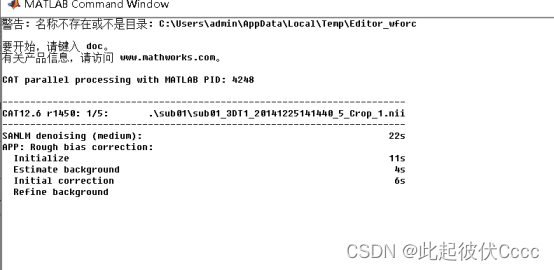

点击后出现如下运行界面:

(4)最终会在每个被试文件夹中生成三个文件夹——mri(分割之后的图像)、report(数据分割过程及结果存)、label。

其中在mri文件夹内有分割后的文件。mwp1对应灰质, mwp2对应白质,report中有分割质量报告。